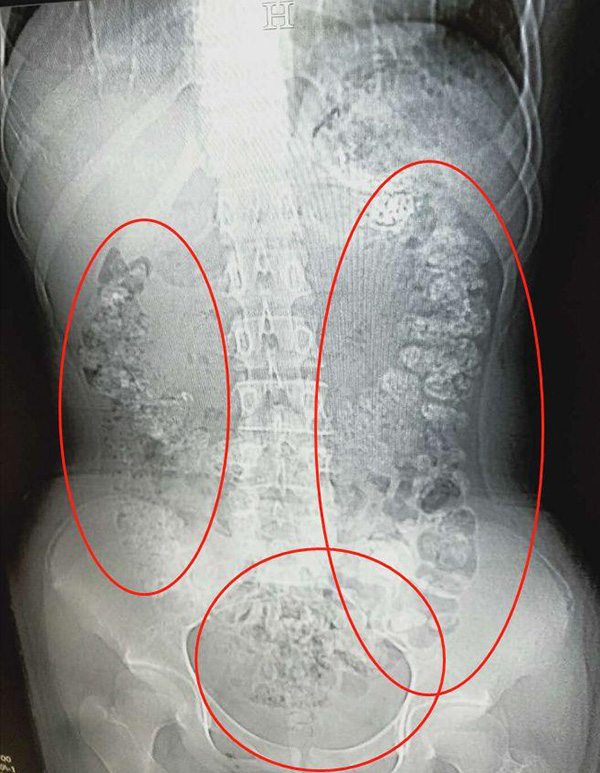

綜合陸媒報導,14歲的小妹妹連續5天沒有排便,不僅沒有胃口,肚子也相當疼痛,由於身體快要承受不住,小妹妹在父母的陪同下到醫院急診。小妹妹一走進診間,醫生就注意到小妹妹肚子鼓鼓的,於是安排腹部電腦斷層掃描,孰料,映入眼簾的畫面讓醫生感到震驚,仔細一看,小妹妹的胃部、橫結腸、升結腸、降結腸、乙狀結腸一直到肛門,都呈現顆粒狀陰影,目測至少超過100顆。

▼小妹妹的胃部一直到肛門,都擠滿未消化的珍珠。(圖/翻攝自浙江24小時)